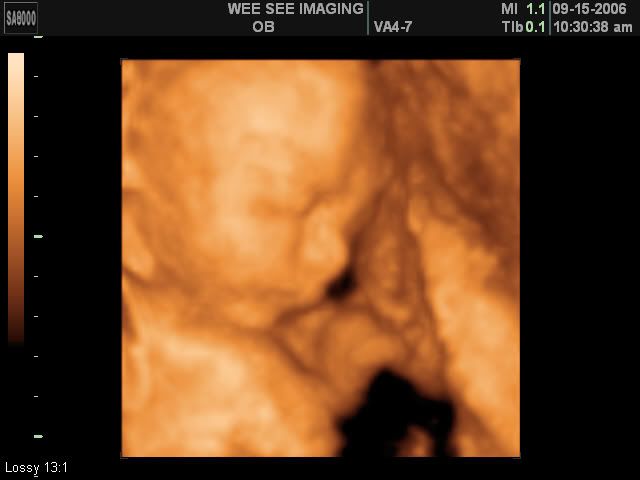

Victoria Rose Kelly

Date Due: December 15, 2006